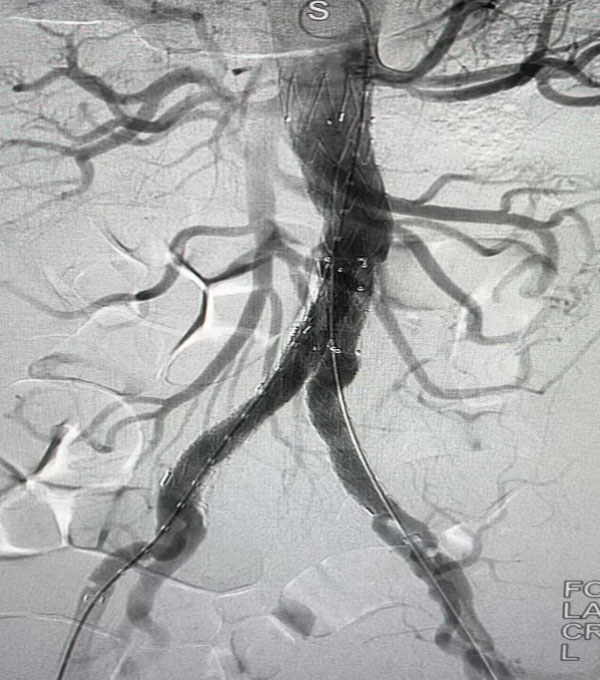

同期,另一臺“升主動脈置換+全主動脈弓置換+胸主動脈覆膜支架腔內隔絕術”正在開展,該病例為一名A型主動脈夾層患者。在主動脈弓及分支成功游離且心臟停跳后,心外科負責人趙永波“轉場”為患者完成了血管置換,心臟復跳成功,止血徹底。隨后,談凌凌主治醫師、侯五輝主治醫師為患者進行胸主動脈腔內修復。下午2點左右,兩臺手術成功結束。通過現場視頻直播,在手術同時,手術人員與大會現場的專家們就影像評估、手術策略、手術器械的選擇及操作技巧等多個環節進行了互動討論,學術氣氛熱烈,大會主席及與會代表給予我院高度評價。緊接著,手術團隊又為一名79歲腹主動脈瘤患者進行了腹主動脈腔內修復手術,效果良好,同樣受到與會專家的好評。

腹主動脈腔內隔絕